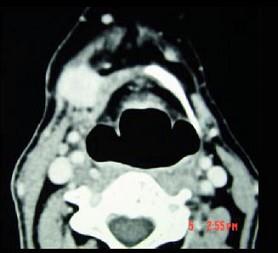

问题 男,45岁,右侧颌下扪及一包块约4个月,无痛,PE:包块质硬,表面欠光整,移动度较差,CT如图所示,最可能诊断是()

选项 A.颌下腺神经源性肿瘤 B.颌下腺腺瘤 C.颌下腺淋巴瘤 D.颌下腺腺癌 E.颌下腺转移瘤

答案 D